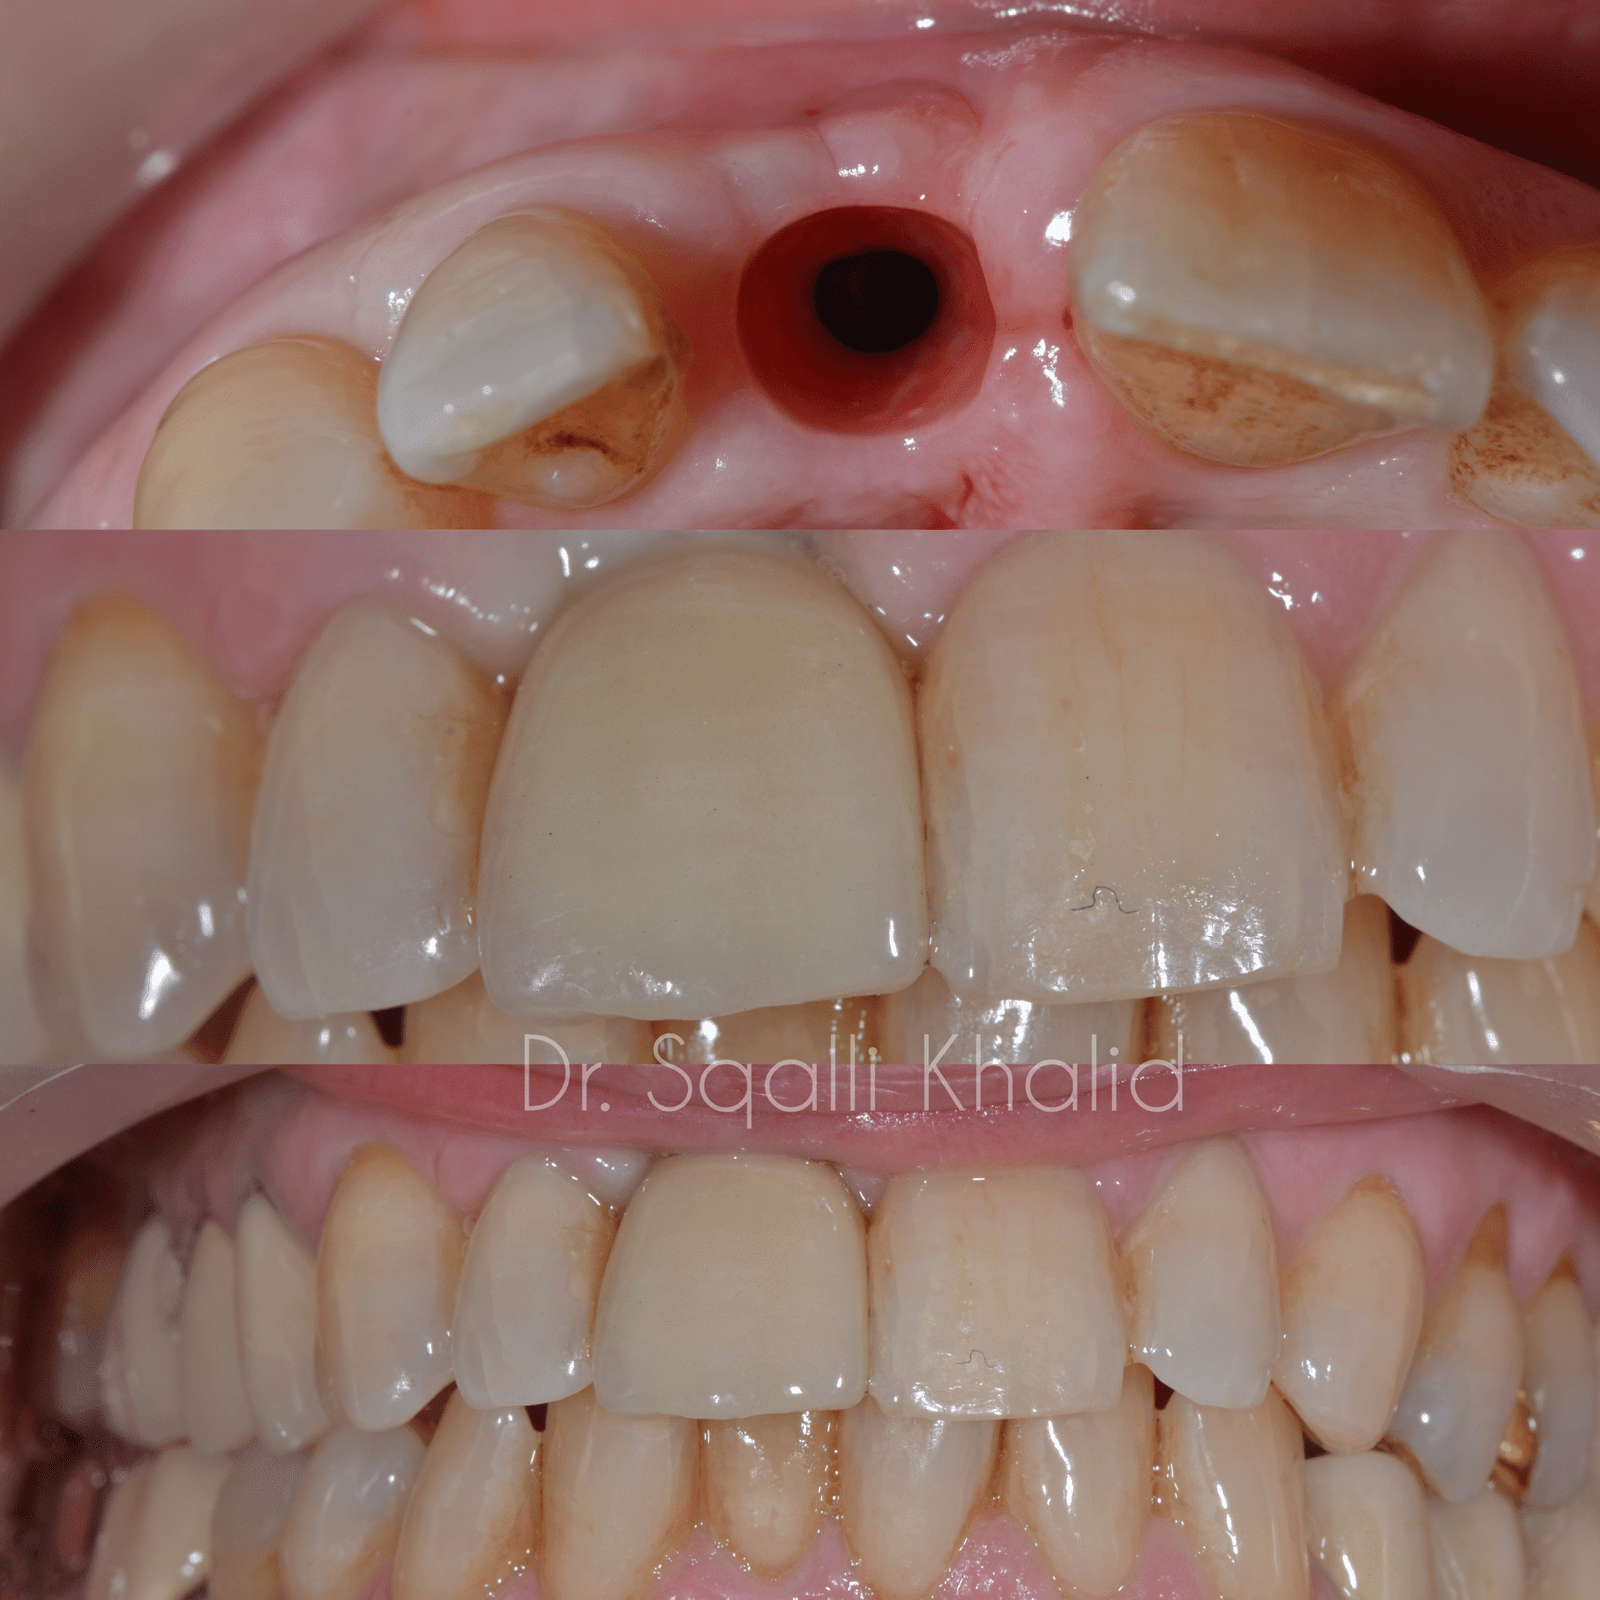

Un implant dentaire est une racine dentaire artificielle en titane biocompatible. Il est placé chirurgicalement dans l’os de la mâchoire et sert de base solide à une couronne, un pont ou même une prothèse complète.

Apparence et sensation naturelles : les implants imitent vos dents naturelles en termes d’apparence et de fonction.

Non – la couronne de votre implant est fabriquée sur mesure pour s’intégrer parfaitement à vos dents naturelles. La plupart des gens ne sauront jamais qu’il s’agit d’un implant.